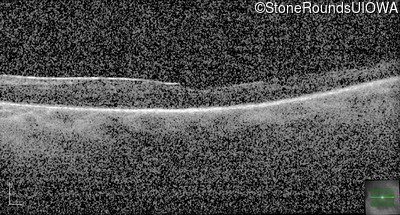

Optical Coherence Tomography - Right - 20/125

Exemplar / OCT Stack

OCT Stack